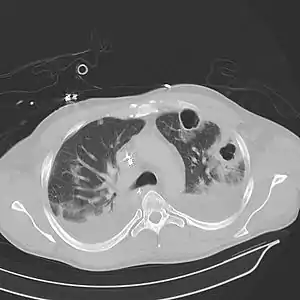

| سیتیاسکن محدوده سینه (بیمار مرد و ۳۷ ساله)که پنومونی دوطرفه همراه با آبسه و حفره را نشان میدهد. | |

رادیوگرافی سینه و سیتیاسکن میتواند شیوهای در تشخیص آبسه ریوی باشد. آبسه ششی بیشتر یکی از ریهها را درگیر کرده و محدوده عمده درگیری شامل لوب بالایی شش در قسمت پسین(پسترال) و در لوبهای پایین(سفلی) در قسمت سقف لوب خود را به صورت حفره خالی در عکس رادیوگرافی نشان میدهد.